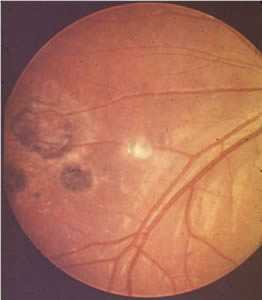

Ocular toxoplasmosis: Chorioretinitis.

Figure A: Severe, active retinochoroiditis.

Figure B: Peripheral retinochoroiditis.

Figure C: Central, healed retinochoroiditis.

Acquired infection with Toxoplasma in immunocompetent persons is generally an asymptomatic infection. However, 10% to 20% of patients with acute infection may develop cervical lymphadenopathy and/or a flu-like illness. The clinical course is usually benign and self-limited; symptoms usually resolve within a few weeks to months. In rare cases ocular infection with visual loss can occur. Immunodeficient patients often have central nervous system (CNS) disease but may have retinochoroiditis, pneumonitis, or other systemic disease. In patients with AIDS, toxoplasmic encephalitis is the most common cause of intracerebral mass lesions and is thought to usually be caused by reactivation of chronic infection. Toxoplasmosis in patients being treated with immunosuppressive drugs may be due to either newly acquired or reactivated latent infection.

Congenital toxoplasmosis results from an acute primary infection acquired by the mother during pregnancy. The incidence and severity of congenital toxoplasmosis vary with the trimester during which infection was acquired. Because treatment of the mother may reduce the incidence of congenital infection and reduce sequelae in the infant, prompt and accurate diagnosis is important. Many infants with subclinical infection at birth will subsequently develop signs or symptoms of congenital toxoplasmosis. Ocular Toxoplasma infection, an important cause of retinochoroiditis in the United States, can be the result of congenital infection, or infection after birth. In congenital infection, patients are often asymptomatic until the second or third decade of life, when lesions develop in the eye.